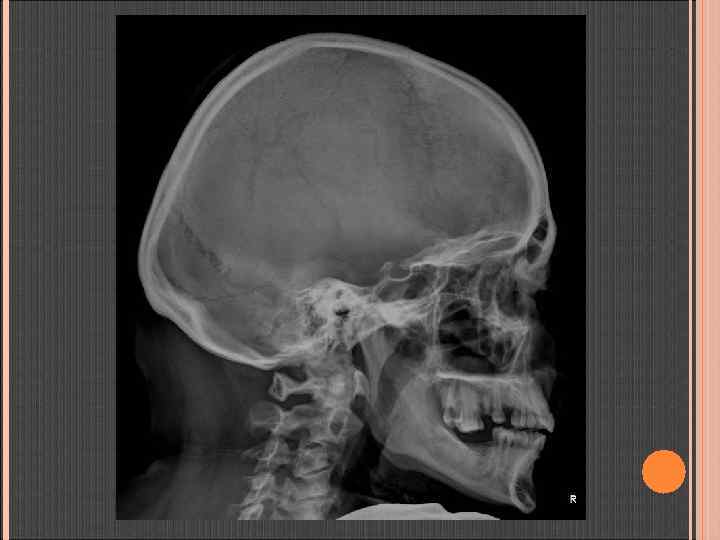

БОКОВАЯ ТОПОГРАММА ЧЕРЕПА ПЛОСКОСТЬ СКАНИРОВАНИЯ Аксиальная проекция Корональная проекция